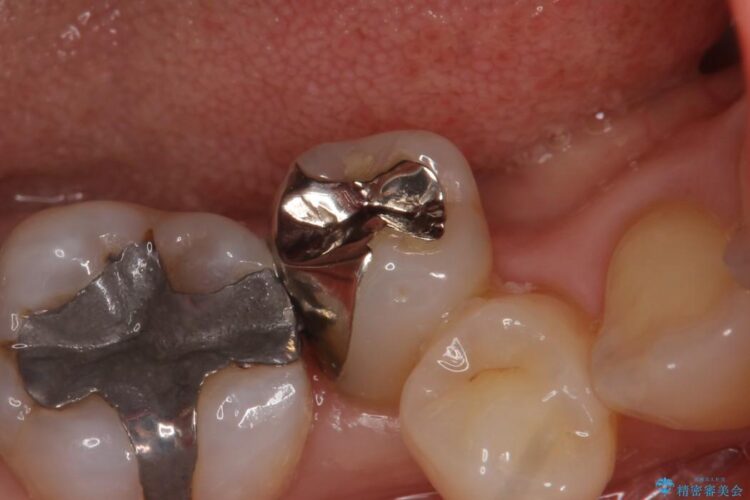

口腔内を調べたところ、右下5番の歯の詰めの下に虫歯を認めました。歯が舌側にズレていて歯磨きをしづらい位置なこともあり、虫歯が再発している状態でした。

虫歯部分を丁寧に取り除き、見た目の問題から患者様のご希望もあり、変性の少ないセラミックインレーを用いて機能と見た目の回復をする計画としました。